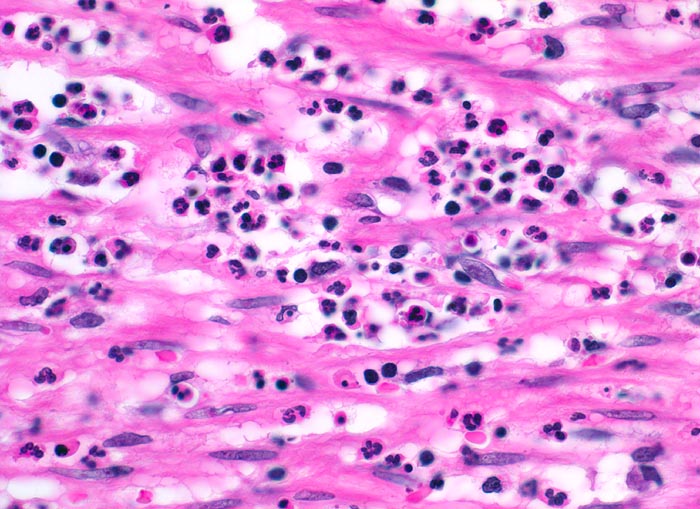

Das histologische Kriterium für eine akute Appendizitis ist die Infiltration der Muscularis propria mit neutrophilen Granulozyten.

• Fokale Ulzeration der Appendixschleimhaut.

• Diffuse Durchsetzung der Appendixwand mit neutrophilen Granulozyten (phlegmonöse Entzündung).